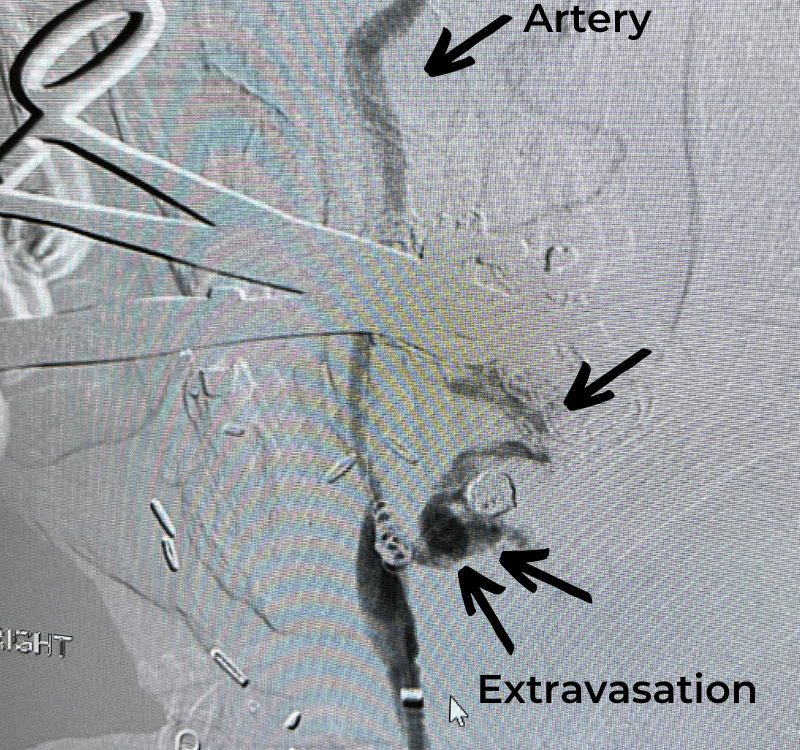

The patient is an 83-year-old man who has a history of hypertension and prior strokes who presented with a brief episode of left arm greater than […]